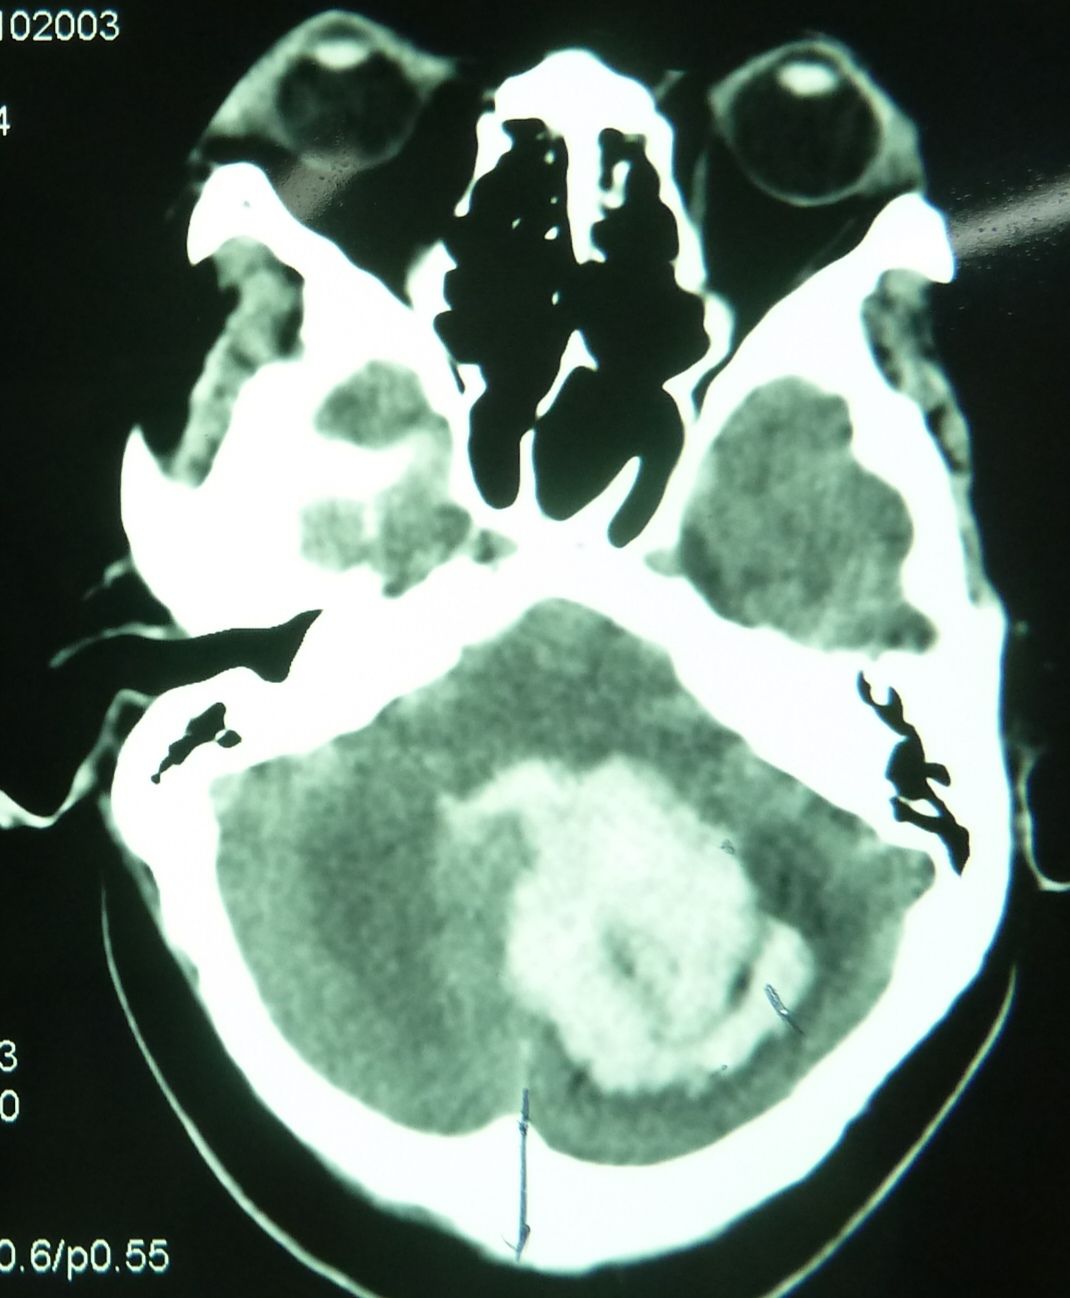

例2,患者女,54岁,突发头痛并意识不清3小时入院,有高血压、冠心病史多年,深昏迷,入院时出现呼吸停止,行气管插管,机械辅助呼吸。

CT示,小脑大量出血破入全脑室并梗阻性脑积水,与家属沟通并签字后急症行脑室外引流术,后颅凹开颅血肿清除术。